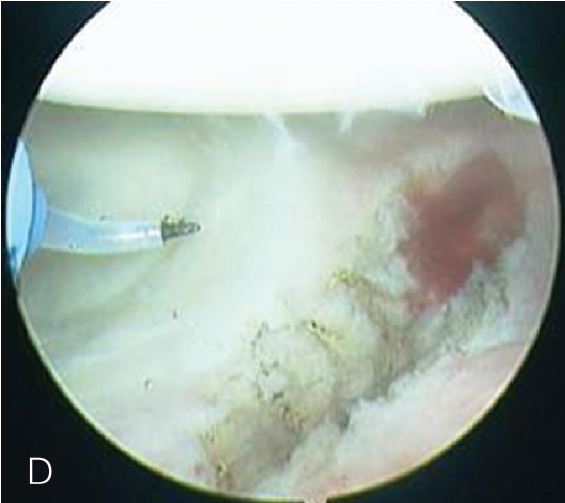

修复处准备

肩袖部分撕裂的修复